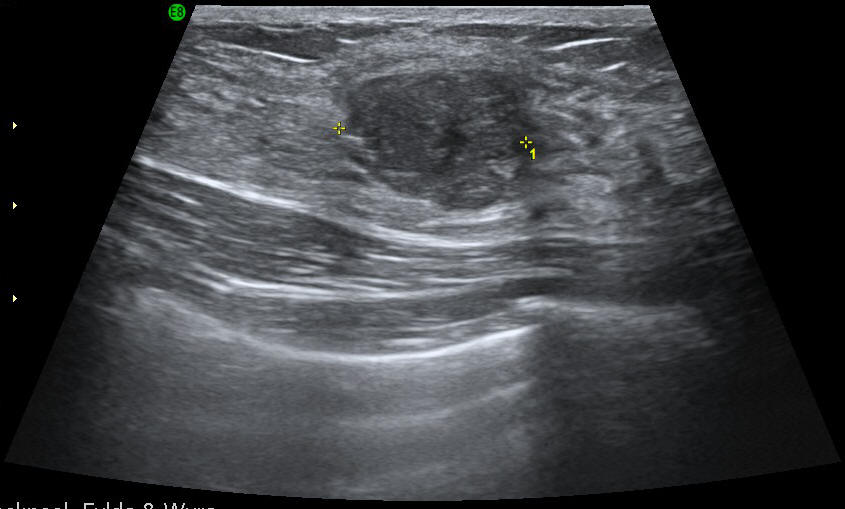

Mammography (Breast Imaging) - Ultrasound

Breast imaging uses x-ray and ultrasound to examine the breast. The most common tests that we carry out are mammography, ultrasound and biopsy.

This type of examination is

mainly performed on women under 40, as well as

men. The examination is painless. A

breast ultrasound takes about 15 minutes,

depending if one of both breasts are being

examined.

The sonographer or the radiologist will ask you to lie on a table. He or she will apply some water-based gel to the breast that is going to be examined, so that the sound waves can be transmitted through the tissue and reach the scanning instrument that is placed on your skin. This instrument is called a transducer, and will be moved in different areas to view the problem from many different angles. You will be able to see the scanned images on the screen while you are having the exam performed.